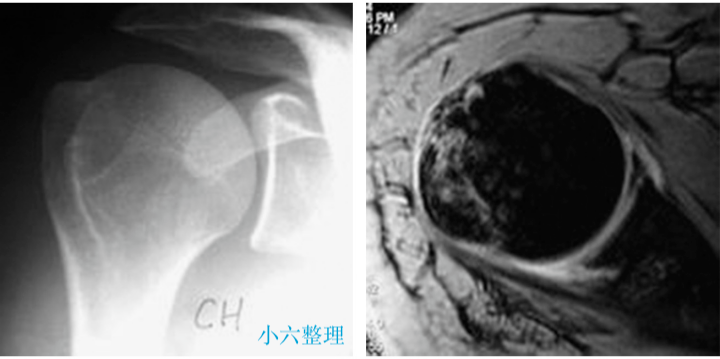

影像学诊断

肱骨大结节骨折 ORIF,术前 X 线片显示肱骨大结节骨折情况;术中暴露肱

肱骨大结节骨折 ORIF,术前 X 线片显示肱骨大结节骨折情况;术中暴露肱